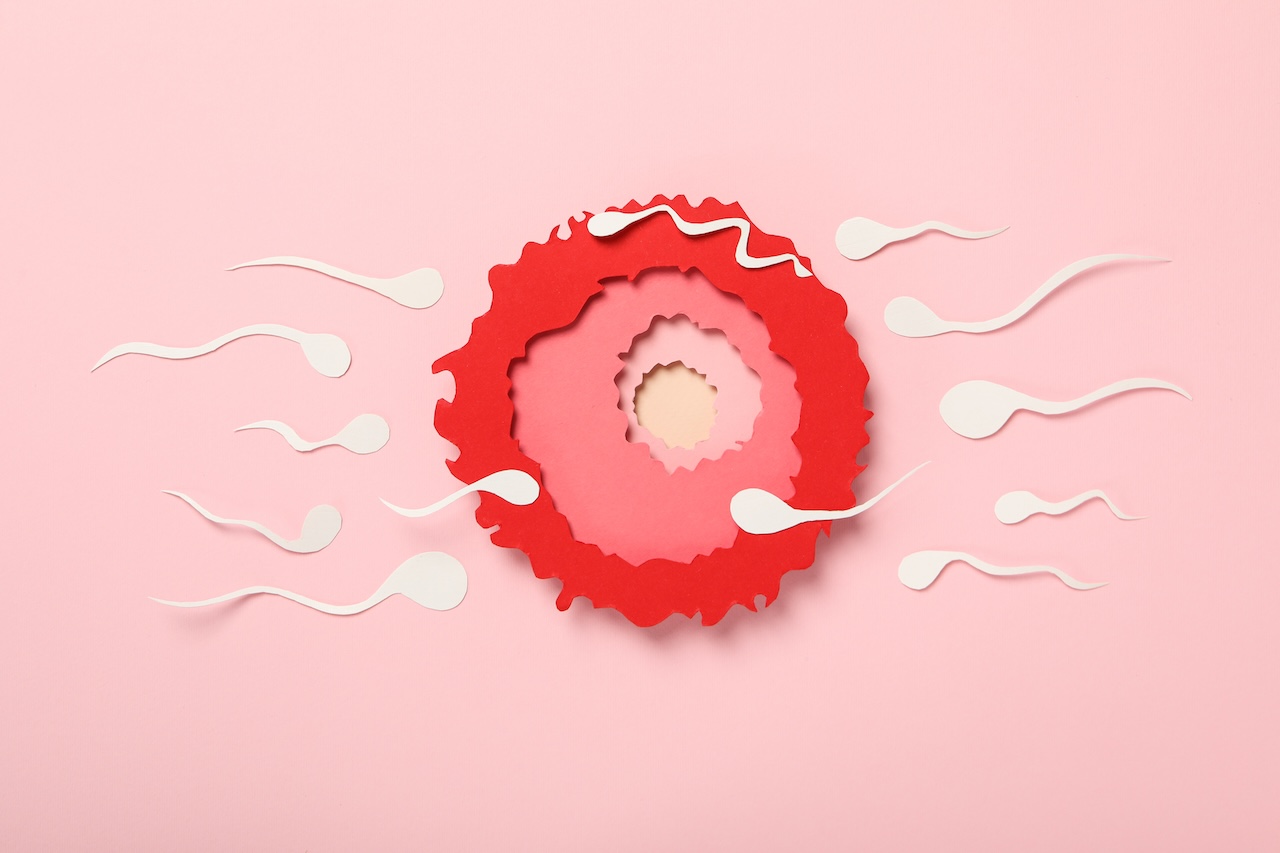

Příprava na IVF: Co vás čeká před přenesením embrya?

16 dubna, 2026